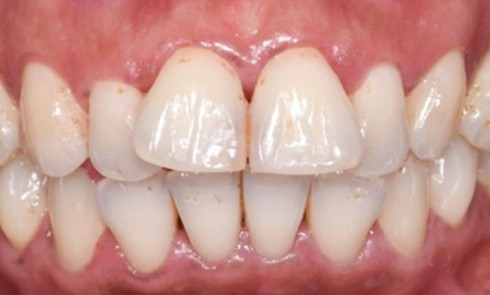

Article réservé à nos abonnés Traitement d’une parodontite stade 3 : application des recommandations S3 de l’EFP en pratique clinique

La Fédération Européenne de Parodontologie (EFP) a organisé en 2019 un European Workshop of Periodontology (EWP) dédié à formaliser des...